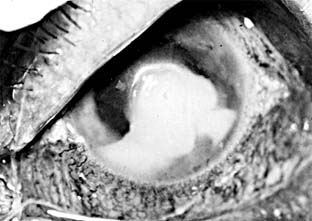

Fungal ulcers are indolent and have a gray infiltrate, often a hypopyon, marked inflammation of the globe, superficial ulceration, and satellite lesions (usually infiltrates at sites distant from the main area of ulceration) (Figure 6-3). The principal lesion-and often the satellite lesions as well-is an endothelial plaque with irregular edges underlying the principal corneal lesions, associated with a severe anterior chamber reaction and a corneal abscess.

Figure 6-3

Figure 6-3: Corneal ulcer caused by Candida albicans.

Most fungal ulcers are caused by opportunists such as Candida, Fusarium, Aspergillus, Penicillium, Cephalosporium, and others. There are no identifying features that help to differentiate one type of fungal ulcer from another.